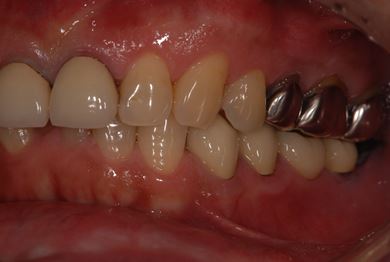

インプラントの症例写真 IMPLANT

インプラント治療

| 性別/年齢 | 男性 / 59歳 | ||||||||||||||||||||||||||||||||

| 主訴 | インプラント治療を検討中。 | ||||||||||||||||||||||||||||||||

| 治療方針 | 欠損部分インプラント治療により、機能的・審美的回復を行う。 | ||||||||||||||||||||||||||||||||

| 治療内容 | インプラント2本、ハイブリッドセラミック2本 | ||||||||||||||||||||||||||||||||

| 総治療費 | 738,675円 | ||||||||||||||||||||||||||||||||

| 治療期間 | 8ヶ月 |